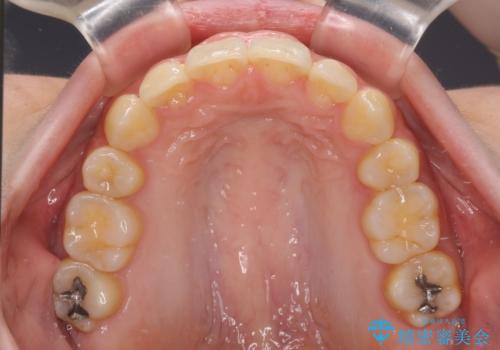

下顎前歯が隠れて突出した口元 ワイヤー装置での抜歯矯正

下顎骨の左右差や、上顎骨の前方位などが認められたため、上下左右の第1小臼歯4本を抜歯し、ワイヤー装置にて矯正治療を行うこととしました。

骨格的な左右差がありましたが、何とか当初予定していた期間で、左右対称の咬み合わせに仕上げることができました。